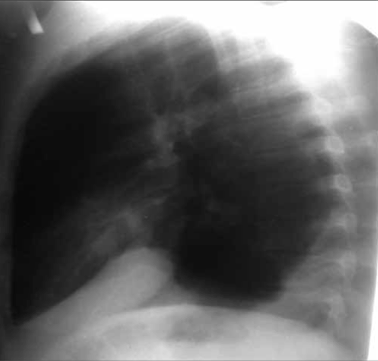

Больной Ж., 22 г. Сочетанная травма. Повреждение левого купола диафрагмы. Картина дислокации органов брюшной полости в левую плевральную полость. Закрытый перелом плечевой кости, закрытый перелом малоберцовой кости. Тяжесть повреждений по шкале оценки ВПХ П. (МТ) — 9,2 балла, ВПХ (СП) — 27

При сочетанной травме тактические подходы к лечению пострадавших необходимо проводить по принципу «Damage control» (7). Устранение повреждений диафрагмы при сочетанной травме является приоритетным. В данном клиническом случае на первом этапе произведена ликвидация разрыва диафрагмы путем ушивания лапаротомным доступом, дренирование плевральной полости. Вторым этапом проведен интрамедуллярный остеосинтез перелома плечевой кости.